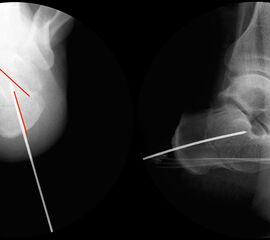

Röntgenaufnahmen des Fußes d.p., streng seitlich und schräg unter Belastung. Saltzmann Aufnahme zur Beurteilung der Rückfussachse.

Operationsplanung anhand der Röntgenaufnahmen unter Beachtung wichtiger radiologischer Landmarks wie Rückfussachse, Metatarsale I – Talushals-Achse im dp und lateralen Strahlengang (Abbildung 1 und 2).

Abbildung 1

Abbildung 2